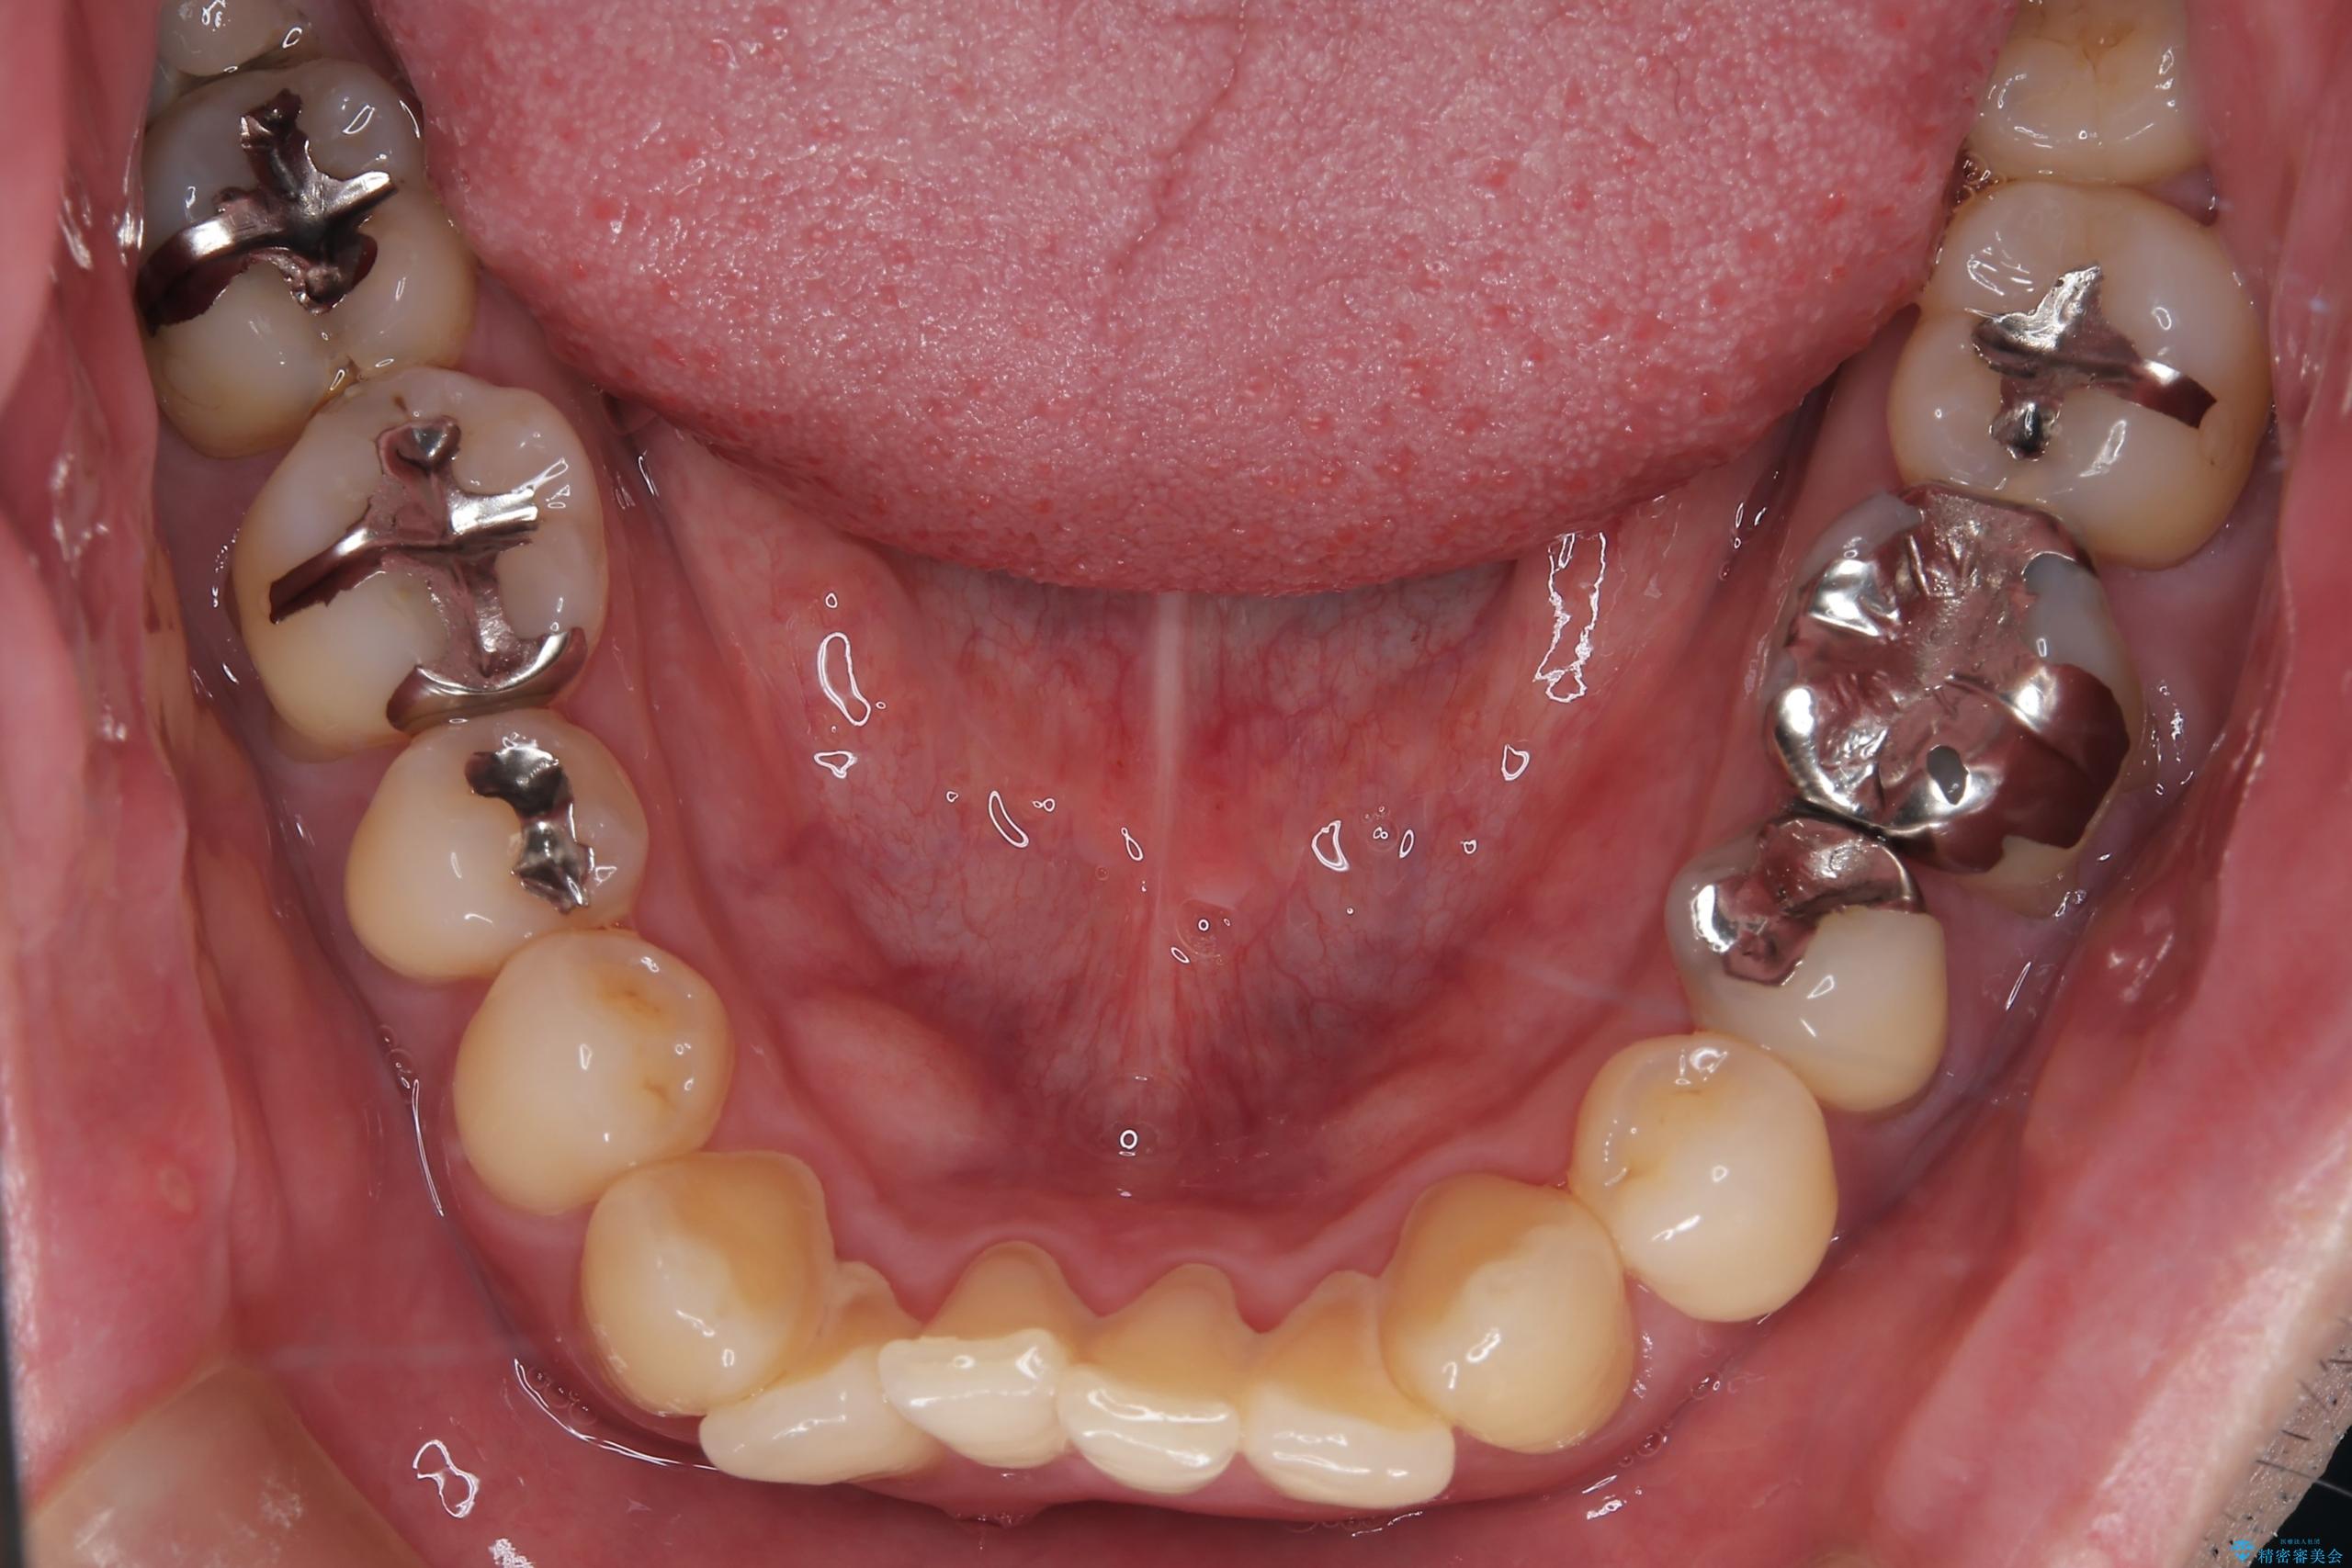

- 右上2番目の歯が舌側転位していることと前歯の叢生(がたつき)を主訴に来院されました。

下のがたつきをとるために、IPR(歯と歯の間を削る処置)も行って歯を並べていきます。